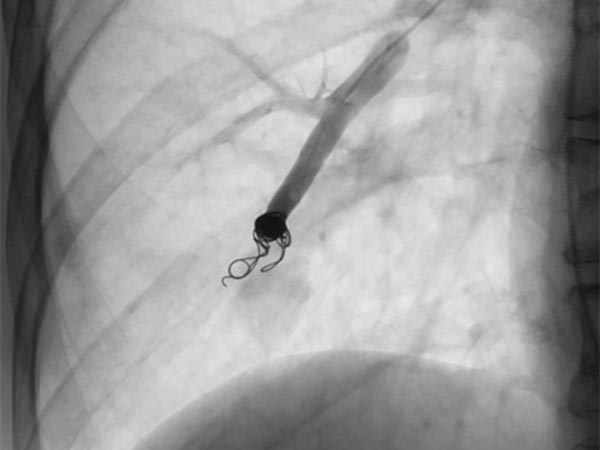

Über das Herz wurde vom Hals (transjugulär) eine Schleuse in die rechte Pulmonalarterie eingebracht, hierüber ein Koaxialkatheter. Nach Injektion von Kontrastmittel zeigen sich auch im rechten Unterlappen Lungenstrombahn pulmonale AVMs.

Nach Sondierung der größeren pulmonalen AVM zeigt sich ebenfalls eine für den Morbus Osler typische Dilatation der direkten arteriovenösen Kommunikation in Form eines Aneurysmas. Der venöse Abstrom ist stark dilatiert, damit ist die Gefahr einer Embolie besonders groß.

Die zuführenden Arterien werden mit mehreren Coils verschlossen. Zur sicheren Verankerung werden Teile der Coils in die arterielle Aufzweigung gelegt (Anker-Technik). Die pulmonale AVM ist verschlossen. Im ehemaligen Aneurysma steht noch etwas Kontrastmittel von einer vorherigen Injektion.